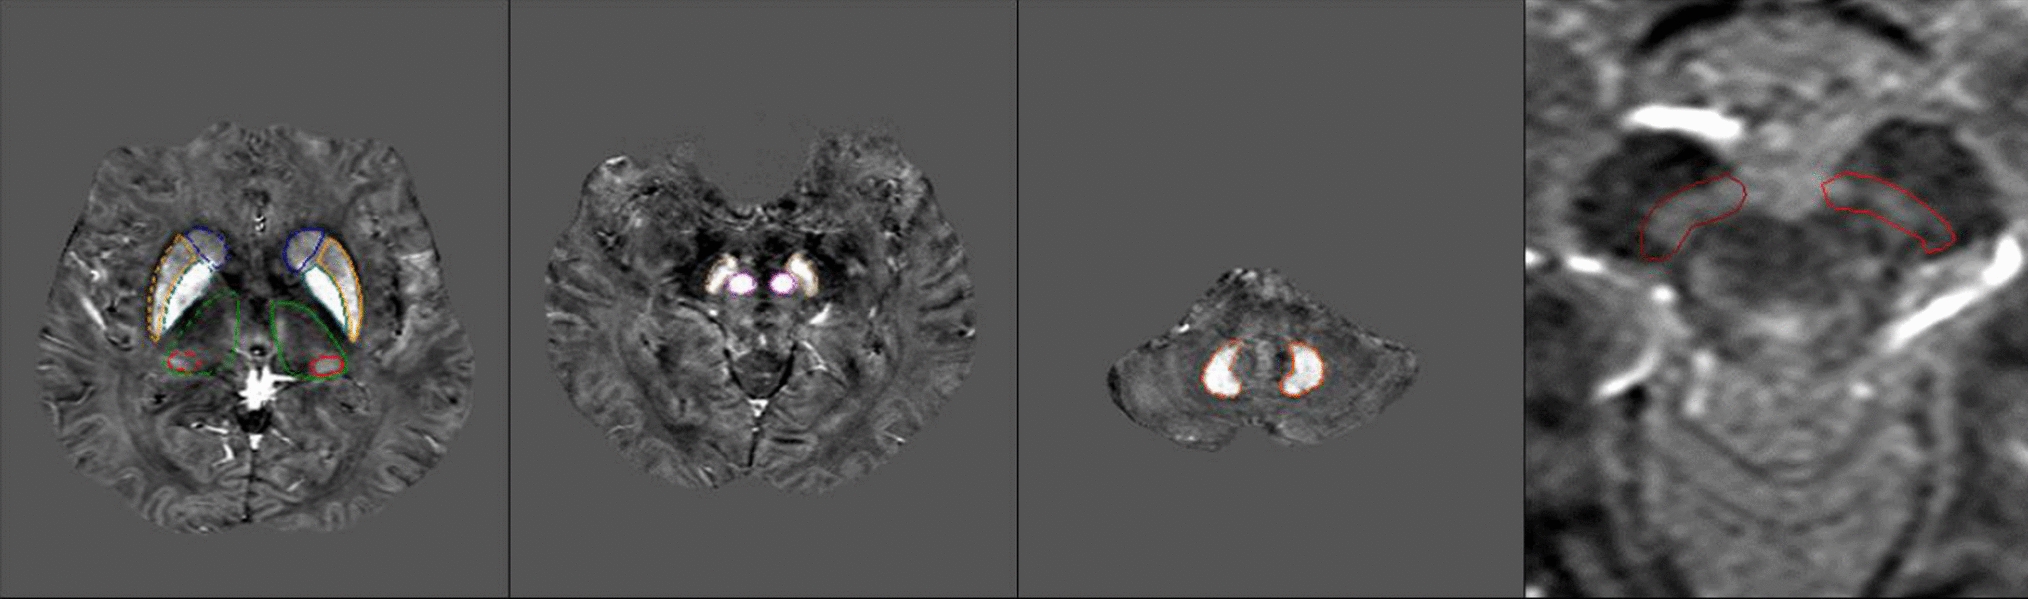

Gencturk M, Ozturk K, Caicedo-Granados E, Li F, Cayci Z. Application of diffusion-weighted MR imaging with ADC measurement for distinguishing between the histopathological types of sinonasal neoplasms. Clin Imaging. 2019;55:76–82.

Ren JL, Yuan Y, Li XX, Shi YQ, Tao XF. Histogram analysis of apparent diffusion coefficient maps in the prognosis of patients with locally advanced head and neck squamous cell carcinoma: comparison of different region of interest selection methods. Eur J Radiol. 2018;106:7–13.

Bi S, Li J, Wang T, Man F, Zhang P, Hou F, et al. Multi-parametric MRI-based radiomics signature for preoperative prediction of Ki-67 proliferation status in sinonasal malignancies: a two-centre study. Eur Radiol. 2022;32(10):6933–42.